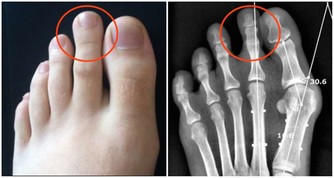

這類體質的人,體溫會比一般人來得低,測量到的體溫大多會低於正常體溫36.5~37 度。長期體溫偏低的結果,就會導致人體免疫力下降3成,比一般人更容易得到感冒、過敏,又或是其他不適的情形。

常出現的其他不適,包括了四肢冰冷、腸胃功能較弱、容易倦怠、活動力不佳等情形,甚至會引發憂鬱症。